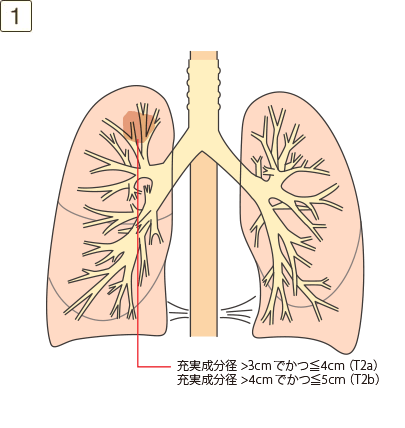

充実成分径>3cmでかつ≦5cm、または充実成分径≦3cmでも以下のいずれかであるもの

T2a:充実成分径>3cmでかつ≦4cm

T2b:充実成分径>4cmでかつ≦5cm